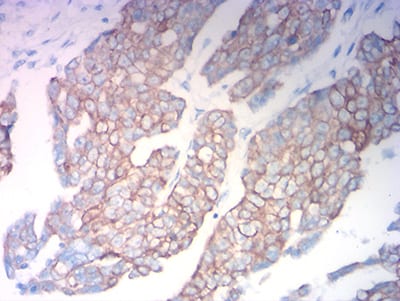

分类: 科研抗体货号: 31757别名: K18; CK-18; CYK18应用: WB,IHC,IF,FCM反应种属: Human

分类: 科研抗体货号: 31772别名: K18; CK-18; CYK18应用: WB,IHC,IF,FCM反应种属: Human

分类: 科研抗体货号: 31755别名: K19; CK19; K1CS应用: WB,IHC,FCM反应种属: Human, Rat